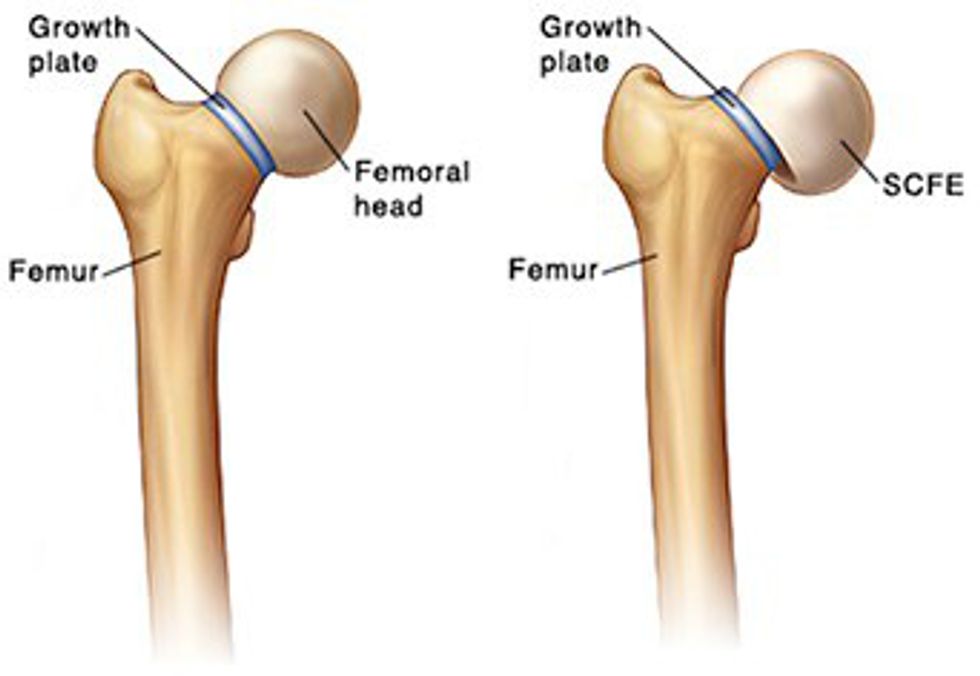

My growth plate, which was supposed to sit on top of my femur, was slipping fast. This incredibly rare genetic phenomenon is known as Slipped Capital Femoral Epiphysis, or SCFE for short. This condition is so rare that there are around two to 10 cases per every 100,000 kids. I would be one of the only cases in the entire state of New Jersey that year, and as a result, I'd be in a bunch of medical journals, because the case has almost never existed in white females of a healthy weight.